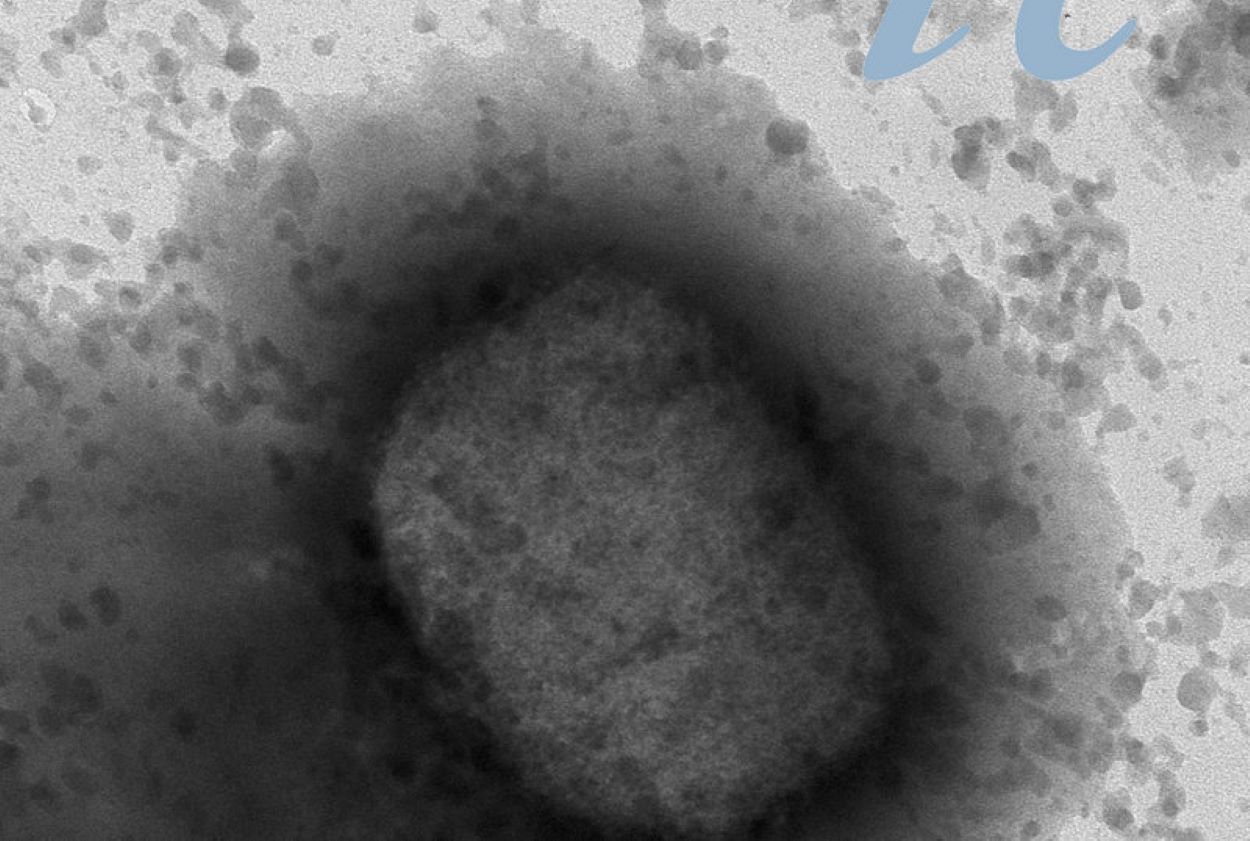

Salut Un organisme nordamericà dona per confirmats quatre casos de verola del mico a Andorra 08/08/2022

Salut Govern alerta del risc de propagacio de la verola del mico si es tenen animals de companyia 03/08/2022

Salut Salut busca tenir al país un petit estoc de vacunes per fer front a la verola del mico 25/07/2022